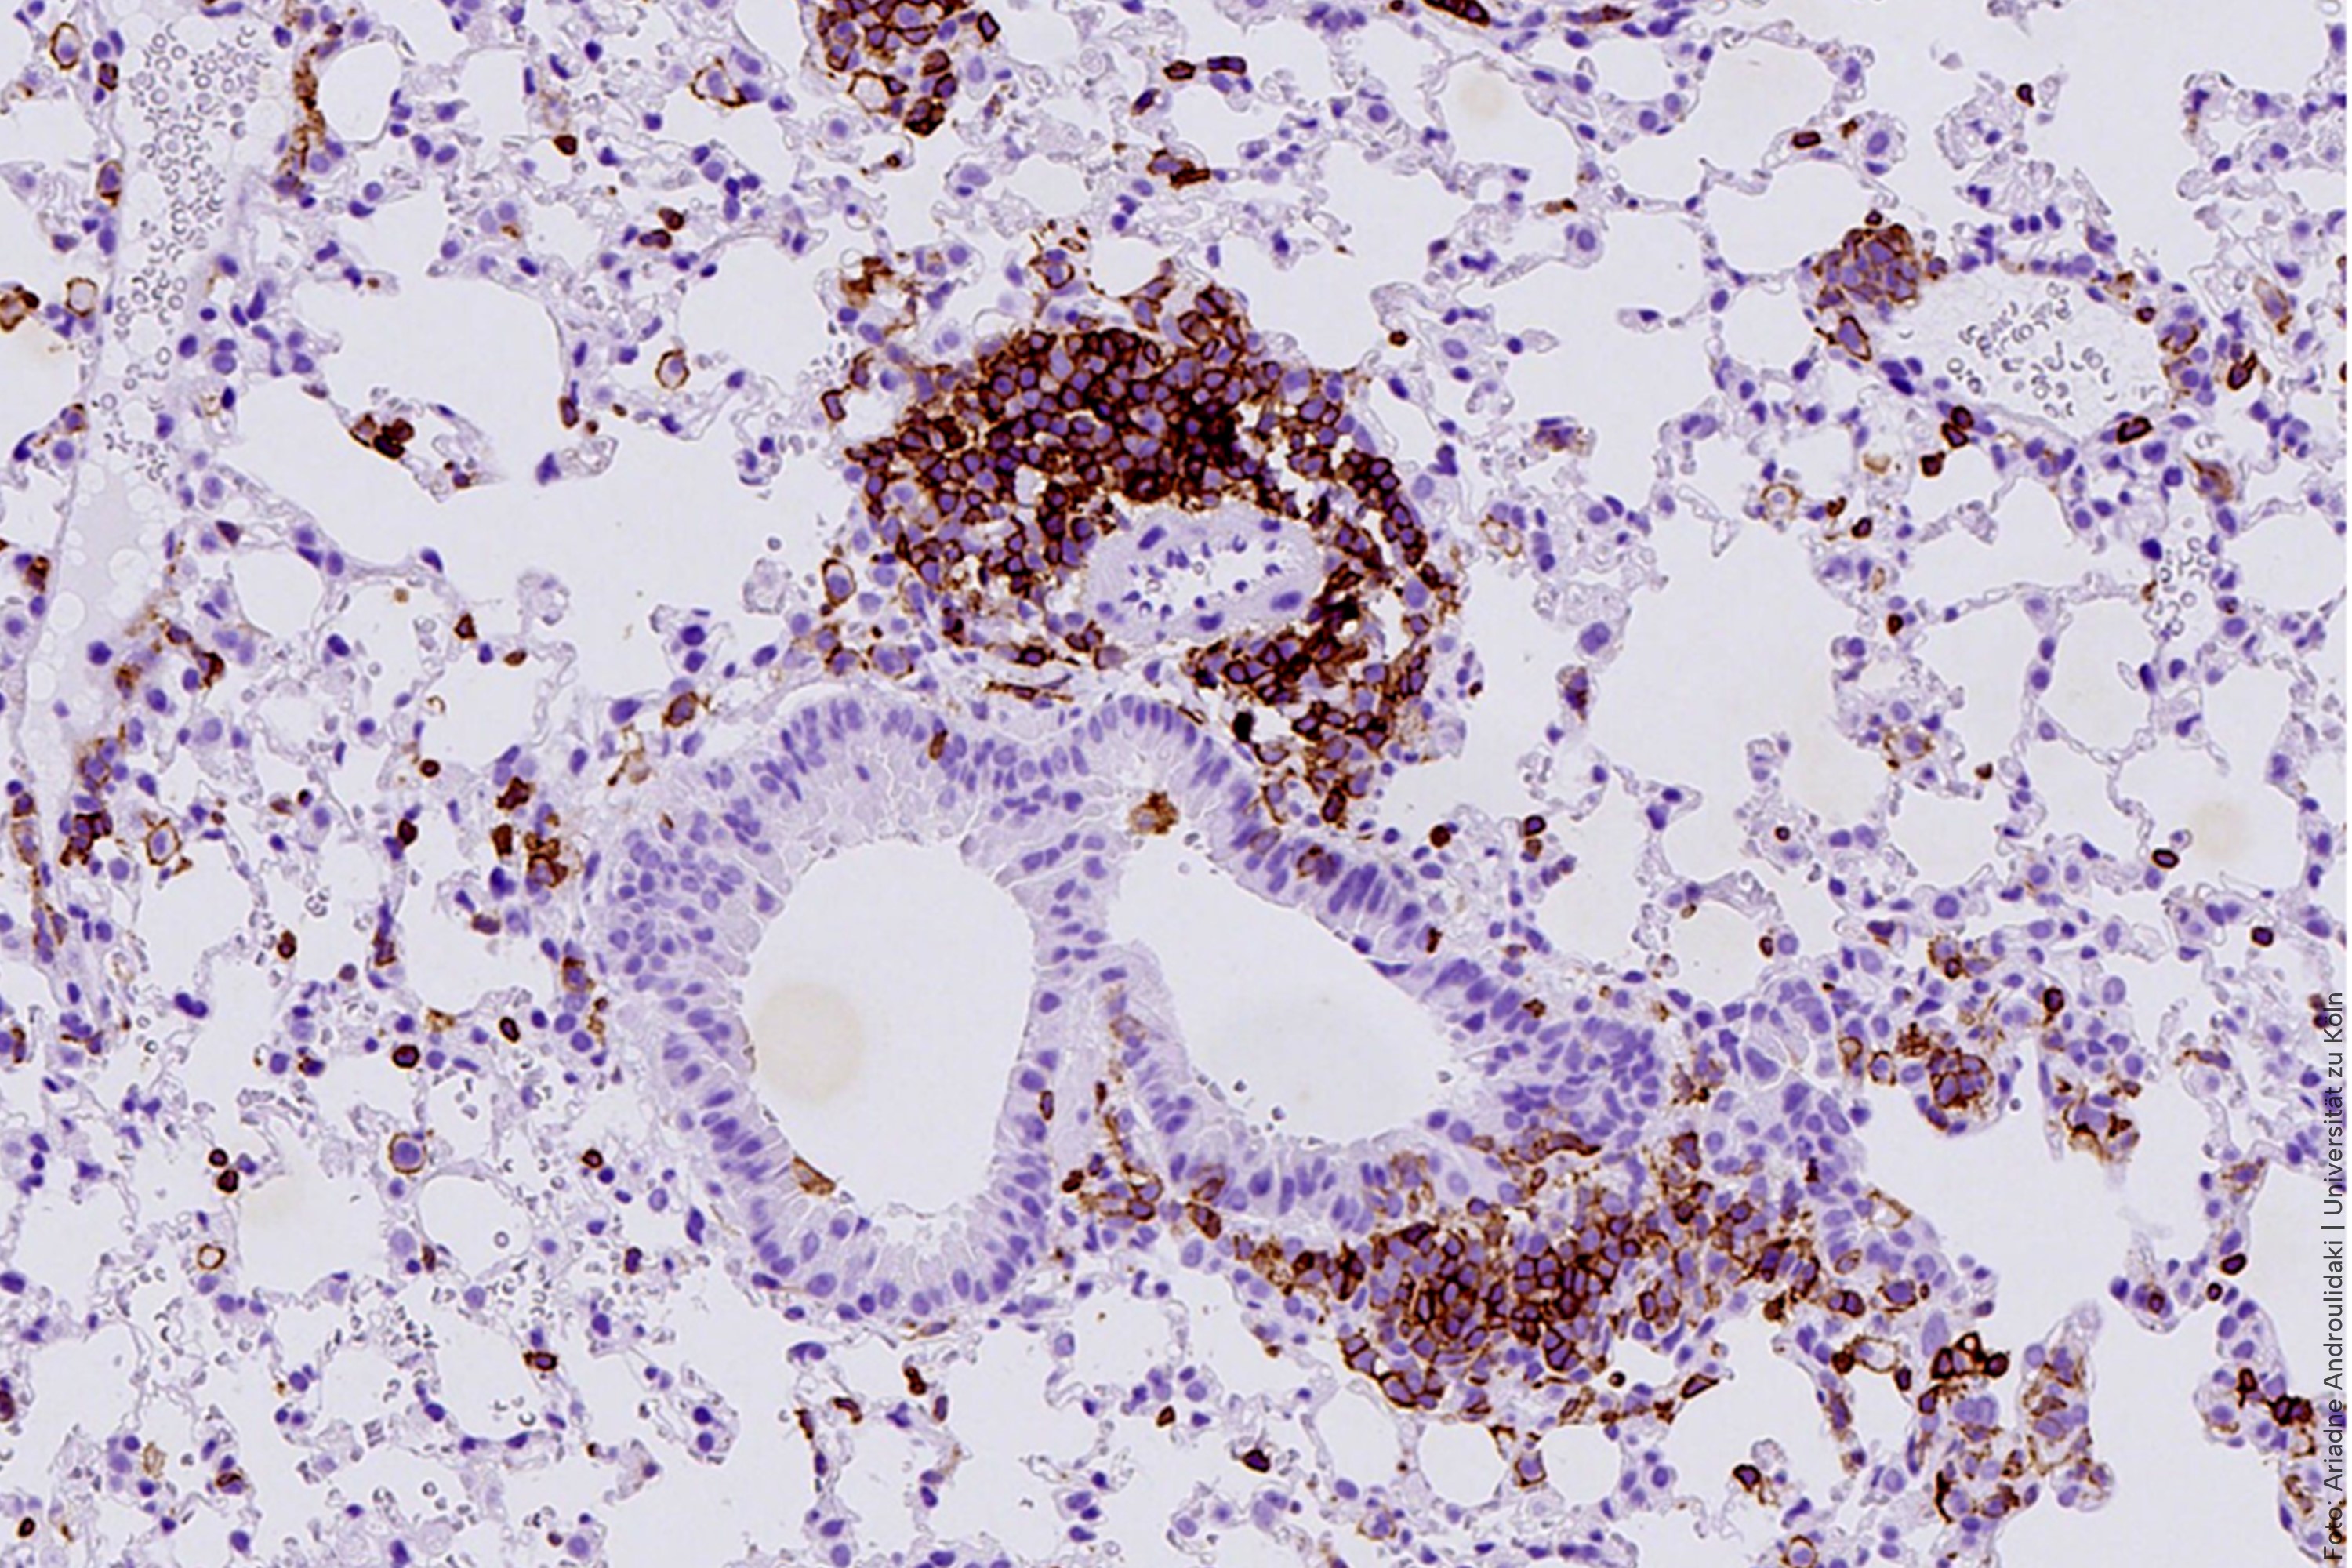

To better mimic the features of human SCLC, the team generated and characterized a novel genetically engineered mouse model lacking caspase-8. Using this new model, the team observed that when this protein is missing, an unusual chain reaction sets off. “The absence of caspase-8 leads to a type of inflammatory cell death called necroptosis that creates a hostile, inflamed environment even before tumors fully form” explains von Karstedt. “We were also intrigued to find that pre-tumoral necroptosis can in fact promote cancer by conditioning the immune system,” she continues. The inflammation creates an environment where the body’s anti-cancer immune response is suppressed, preventing immune cells from attacking threats like cancer cells. This, in turn, can promote tumour metastasis. Surprisingly, the researchers observed that this inflammation also pushes the cancer cells to behave more like immature neuron-like cells, a state that makes them better at spreading and that is associated with relapse.